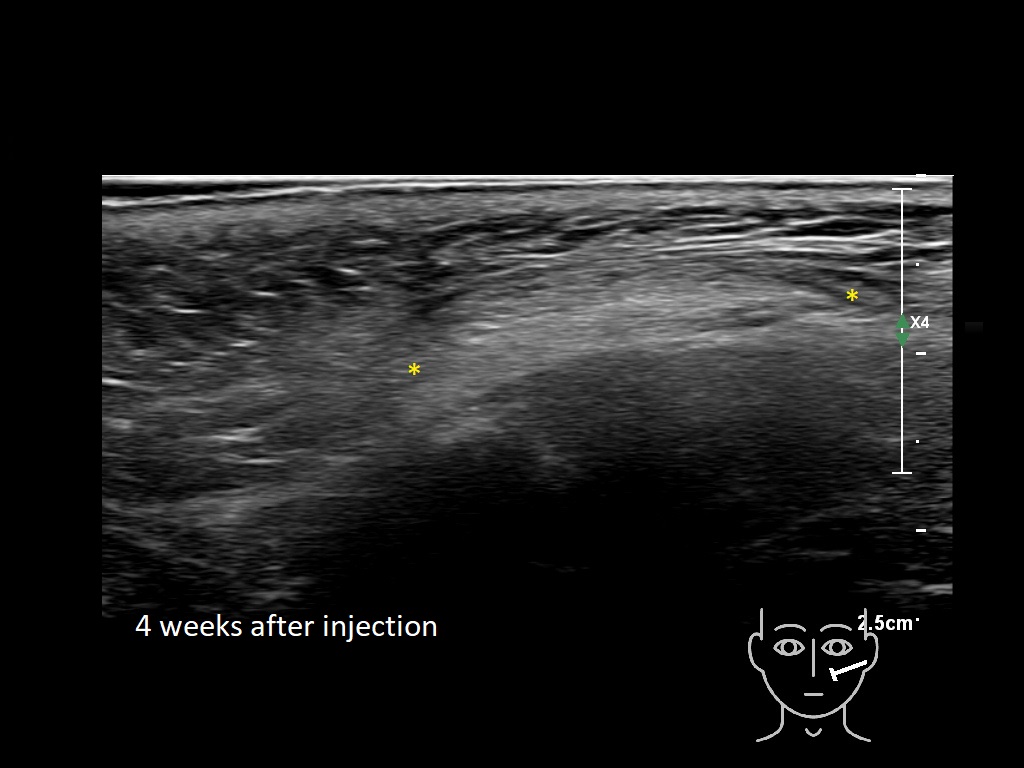

Draw in the second image below where the fillers are located. To check if your answer is correct, swipe the first image to the right.